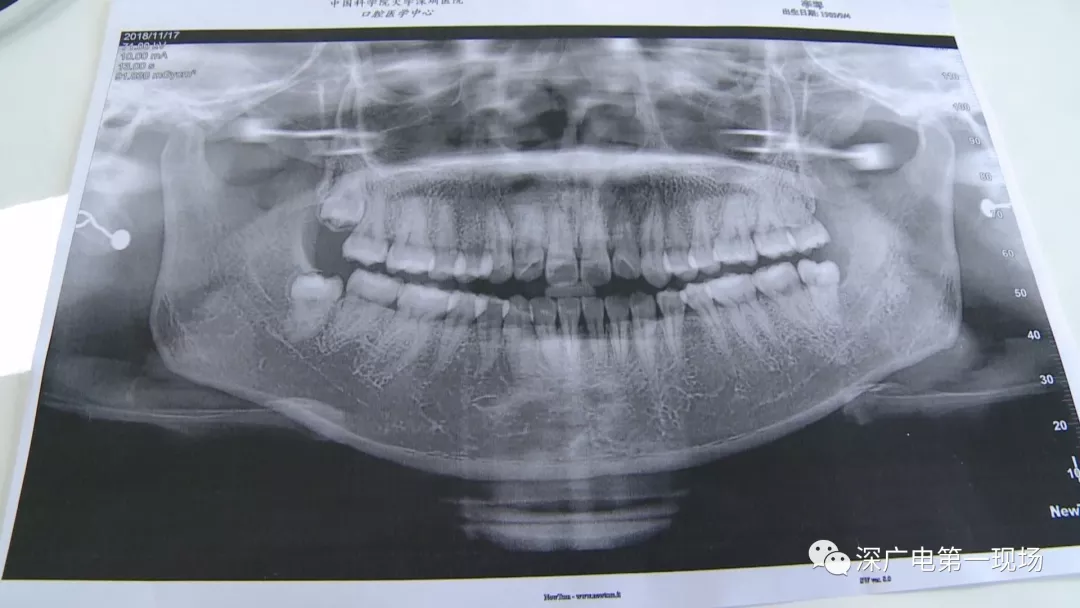

針對李女士的情況,醫(yī)生介紹,當(dāng)時要想拔出李女士的這顆智齒,難度還是很大的,屬于復(fù)雜智齒的拔除術(shù)。她的風(fēng)險在于距離神經(jīng)管近,同時這顆牙齒完全埋在牙床最后的位置,直接往外拔,會加大頜骨的風(fēng)險,因此需要先切開,讓牙齒暴露后,切小再慢慢地拔出。